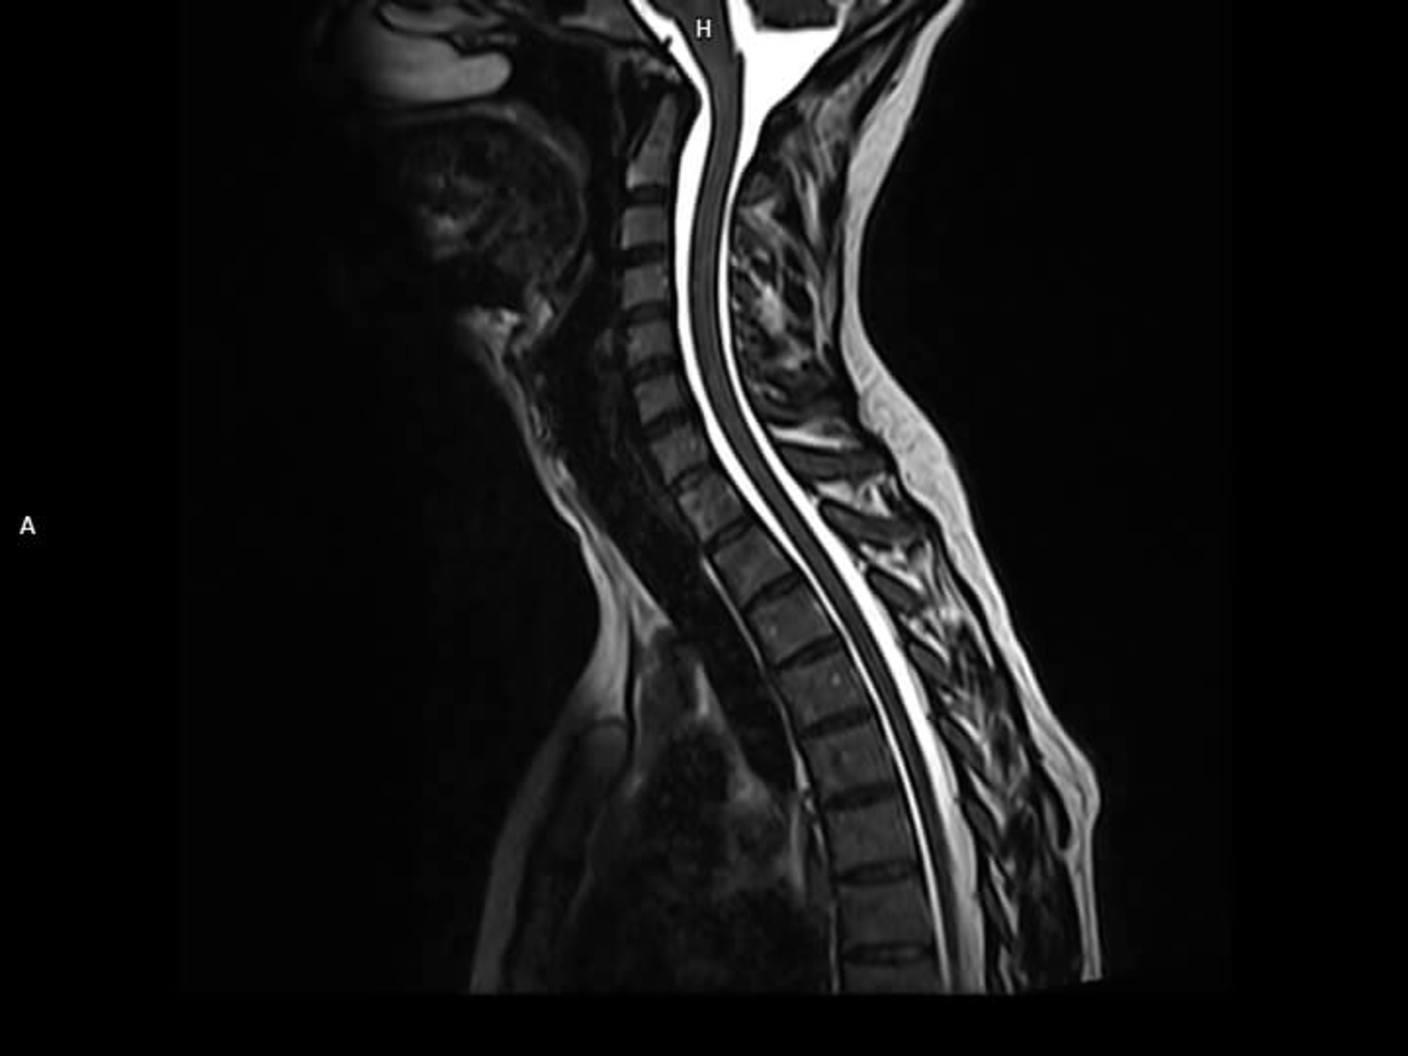

Sagittal T2 3D SPACE-MAGNETOM Altea

Sagittal T2 3D SPACE-MAGNETOM Altea/Coil-HeadNeck20, BY12, SP32